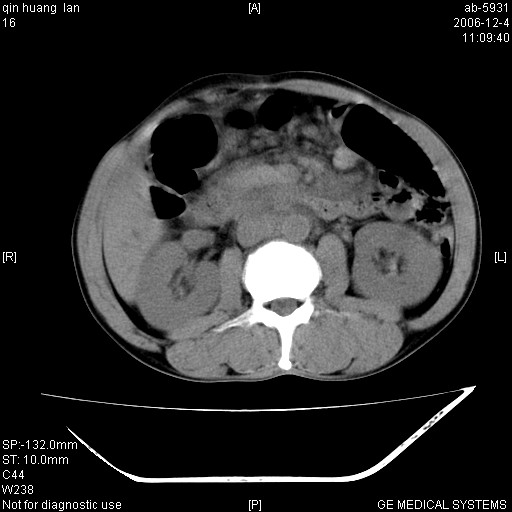

以下是引用liaoqiang在2006-12-4 15:49:00的发言:[br]1.考虑肝门区胆管细胞癌伴肝门区和腹后淋巴结肿大。2.胆总管胰腺段扩张,其下端管腔狭窄,壁厚,胰头大。考虑胆总管下段有转移灶或肿大淋巴结压迫所致。

以下是引用qiuleiyu在2006-12-4 19:07:00的发言:[br]1、无基础肝硬化表现。[br]2、左右肝内胆管明显软藤样扩张。[br]3、肝门区肿块,呈现延时花瓣样强化。而非快进快出强化。[br]4、胰头大,然密度较均,未见双管征。[br]5、后腹膜多发淋巴肿大。[br]考虑肝门部胆管ca伴胰头及后腹膜广泛淋巴转移及胆总管扩张。必要时mrcp进一步检查。

以下是引用jinguoji在2006-12-5 13:08:00的发言:[br][br]肝门区胆管细胞癌 并肝门、胰头周围、腹后淋巴结肿大转移。